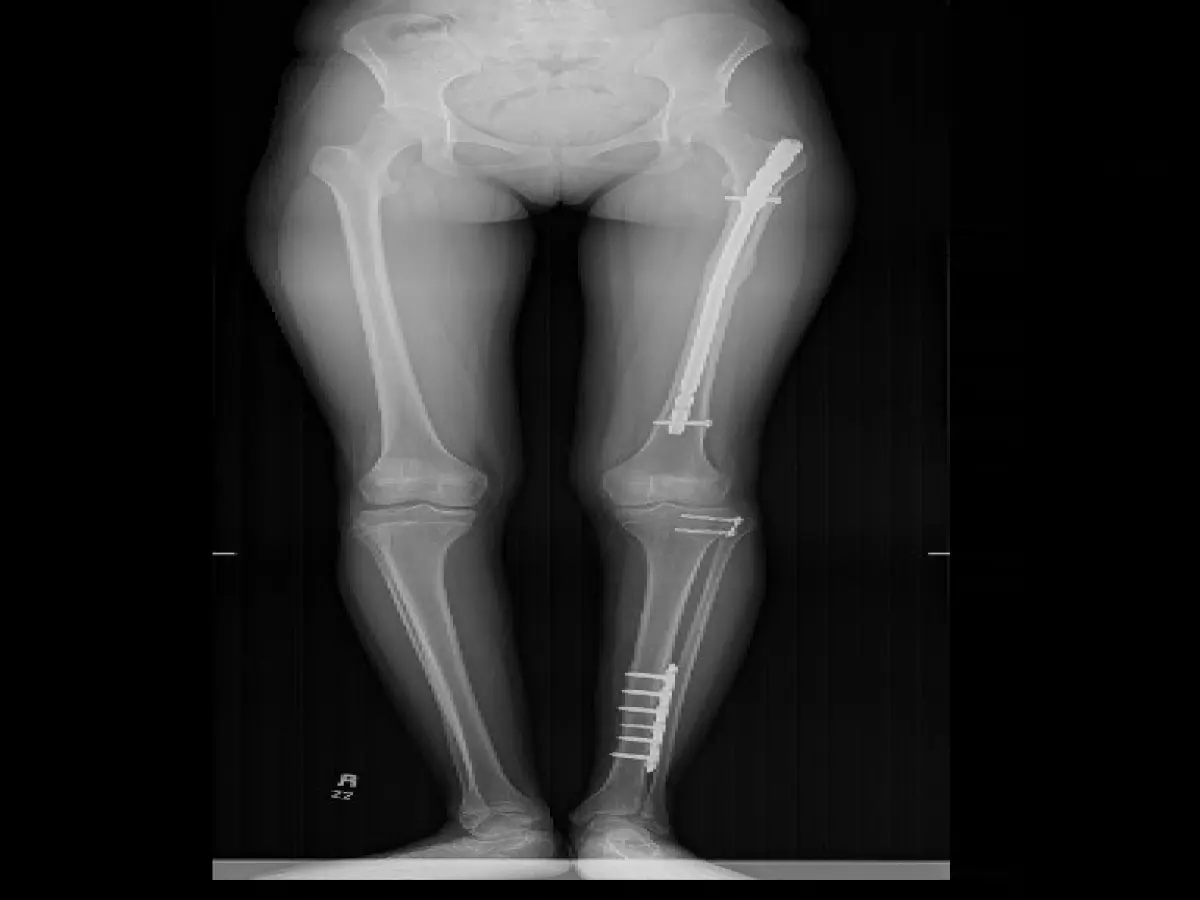

العظم الزجاجي هو مرض وراثي يؤدي الى كسور متعددة وتشوهات/تقوسات في العظام. تعالج الكسور في أول سنتين بالعادة بالجبس ...

بخلاف الكسور العادية في الاطفال فإن مثل هذا الكسر يحدث دون اصابه والتآمه صعب. في حال التآمه بعد التدخل الجراحي ...